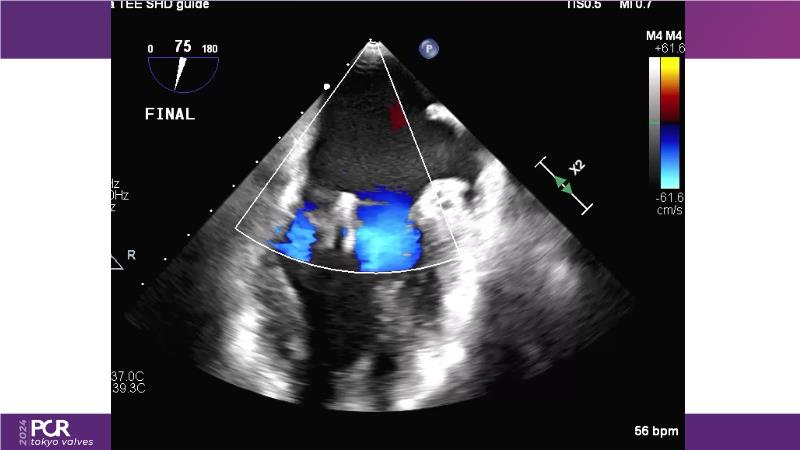

Watch this session to get an overview of a new TEER device, follow the step-by-step procedure related to initial experiences with this device for a Japanese patient with degenerative mitral regurgitation, learn about the latest data from RCT and registries, and follow discussions of challenging TEER cases!